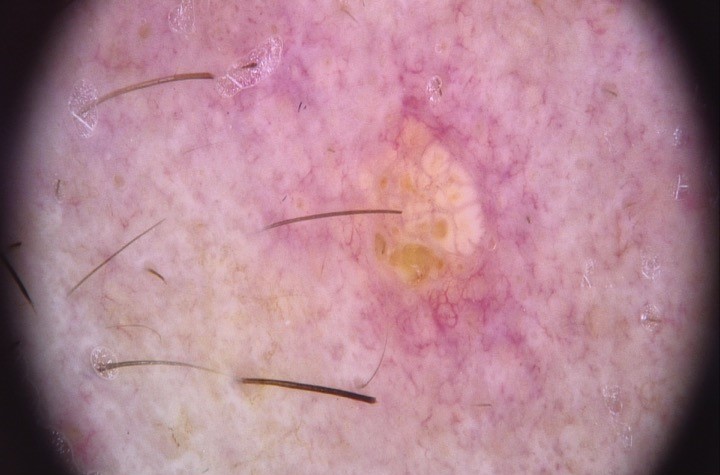

Clinical images

- Clinically presents as a yellow or pink-tan papule or nodule

- Clinically can be mistaken for basal cell carcinoma